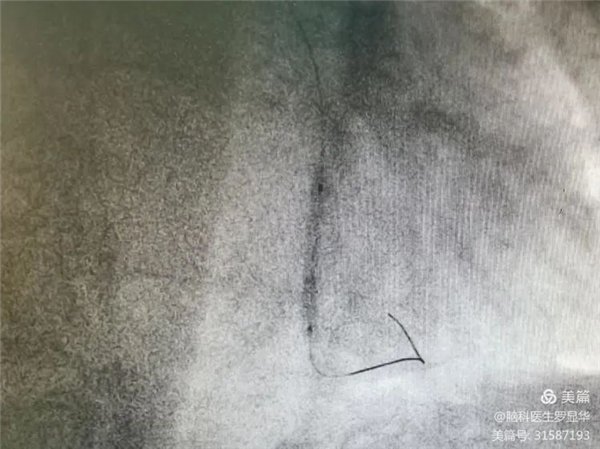

手術(shù)過程:指引導(dǎo)管到位